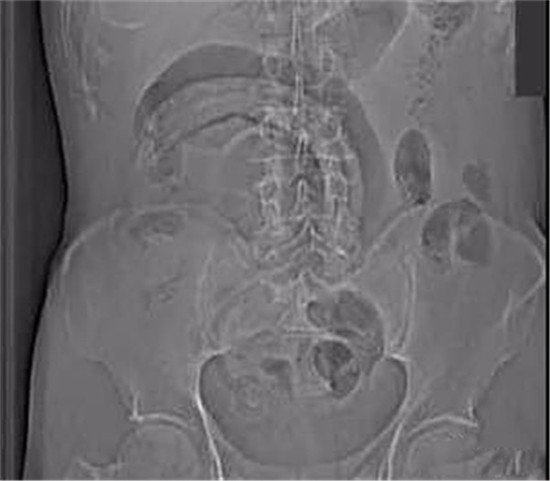

医生给他检查的时候,发现已经有腹膜炎症状,怀疑肠梗阻,拍了个片子,就是上面那个片子:一条大黄鳝在肚子里。

考虑到他已经有腹膜炎的症状,说明肠子已经有个地方破了。只能动手术了。

把肚子打开后,发现大肠破了个洞,黄鳝的头,就在那个洞里。他肚子里都是大便。他的肠子水肿很厉害。黄鳝堵住了大肠,肠梗阻,导致大肠坏死穿孔了。

这种情况下,就是把大肠的洞补起来,洞也长不好。只能造瘘了。也就是在破了个洞的地方把大肠割断,肚皮上挖个洞,大肠拖到肚皮外面,以后的大便从肚皮上排出来。等肚子里炎症消退后,再把大肠放回肚子里接回去。这样他要动2次手术。

就这样,他死里逃生了。

该病人提供的病史,是自己把活泥鳅和黄鳝生吞下去所导致。其实,医生一看泥鳅和黄鳝的颜色以及肠穿孔的部位,就知道怎么回事了。